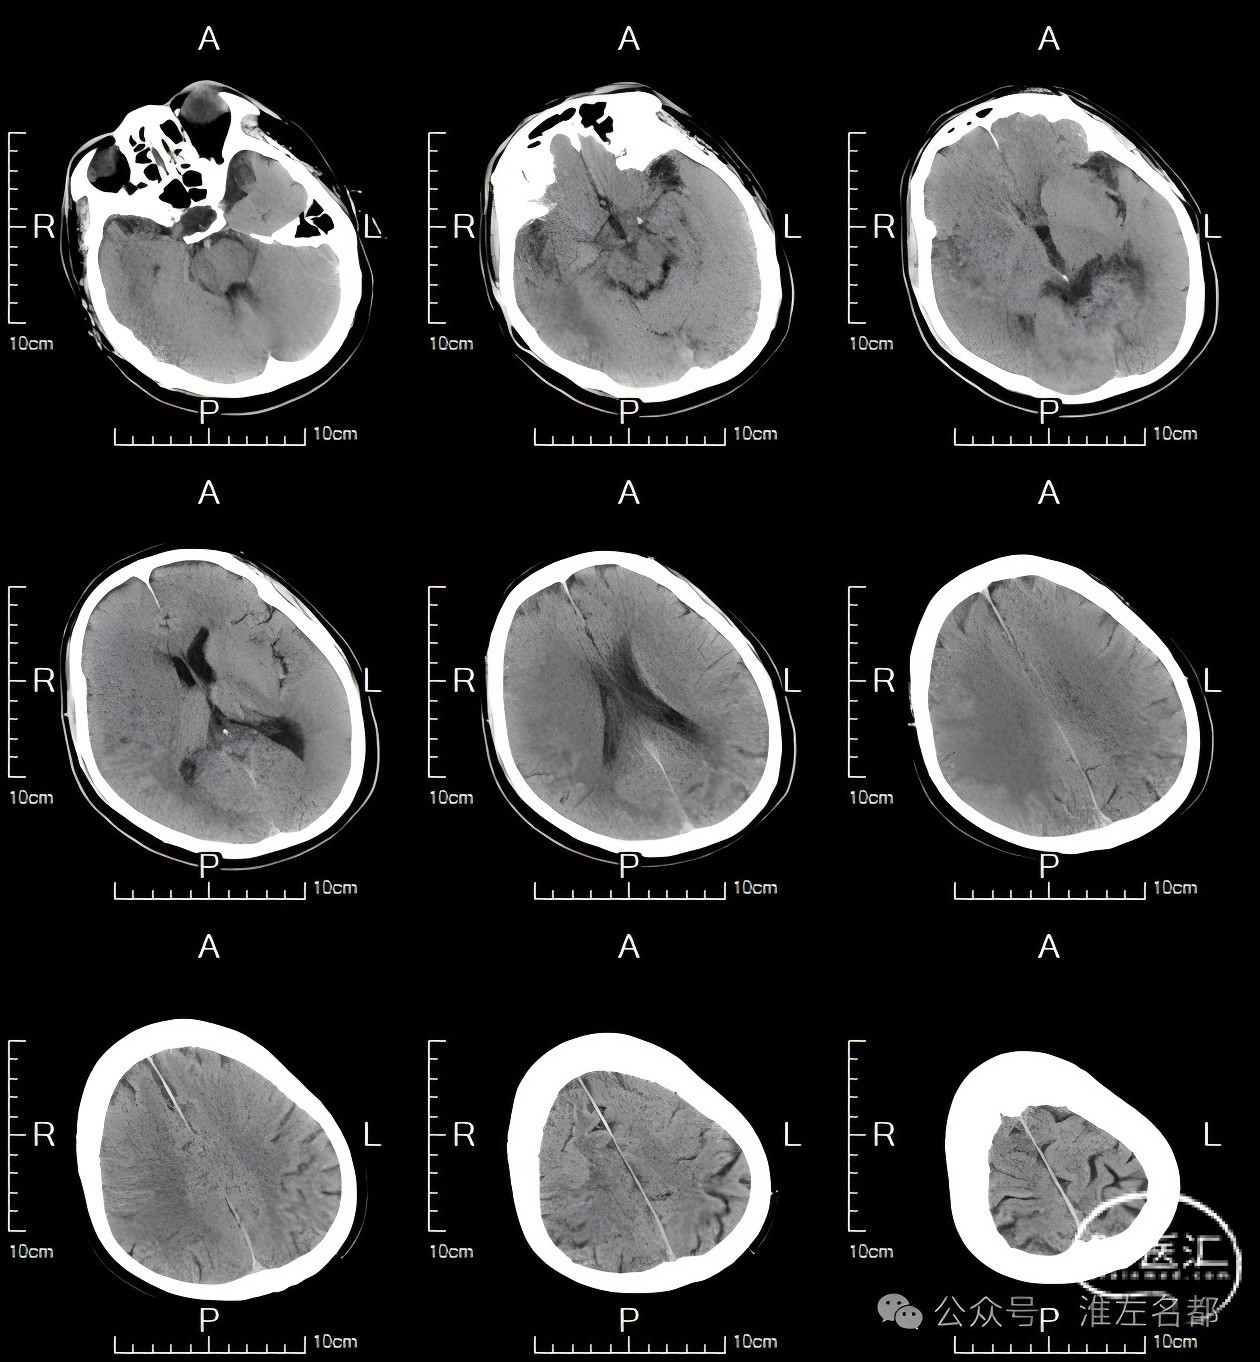

术后第4天MRI

DWI:右侧基底节和额颞叶大范围高信号。

颅脑3D-TOF-MRA:右侧大脑中动脉和双侧大脑前动脉显影通畅。

术后3个月随访,神经功能恢复好,mRS-1。